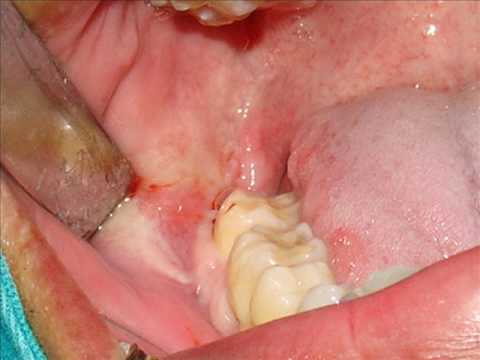

provocándoles daños severos, Otro padecimiento es la Pericoronitis, la cual es un proceso

infeccioso que se presenta al inflamarse la zona donde esta erupcionando el

diente. Provoca mucho dolor, y la

infección puede evolucionar hasta la formación de un absceso, que podría

extenderse a la mejilla y cuello ,

limitando la apertura de la boca.